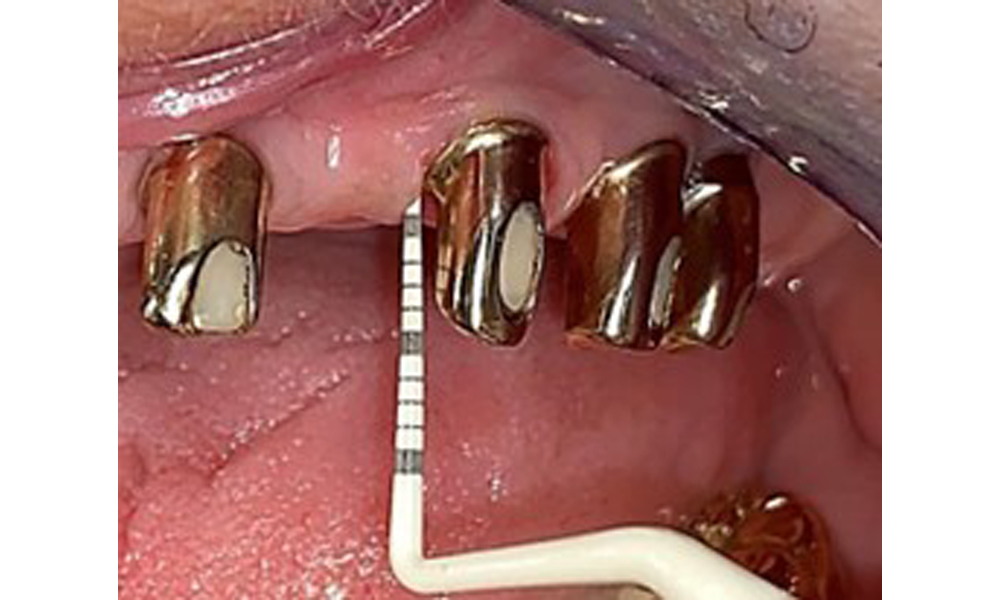

The dental findings are as follows: Combined removable implant and tooth-supported telescopic prostheses on implants 15, 13, 21, 23, 24, 25 and tooth 11 (Fig. 1, Fig. 2, Fig. 3). The patient was fitted with a fixed mandibular denture. Adequate bridges were present over 37 to 34 and 45 to 47 (Fig. 4), the crown margins were intact and there were no active caries. A composite filling with a marginal gap was present on tooth 43. There was mandibular gingival recession, exposing 1 to 3 mm of root surface. This also applies to 11.

Occlusal view: Maxilla with tooth and implant-supported telescopic prostheses.

Fig. 2: Occlusal view: Maxilla with tooth and implant-supported telescopic prostheses

Occlusal view: Maxilla with removable, palateless denture.

Fig. 3: Occlusal view: Maxilla with removable, palateless denture.